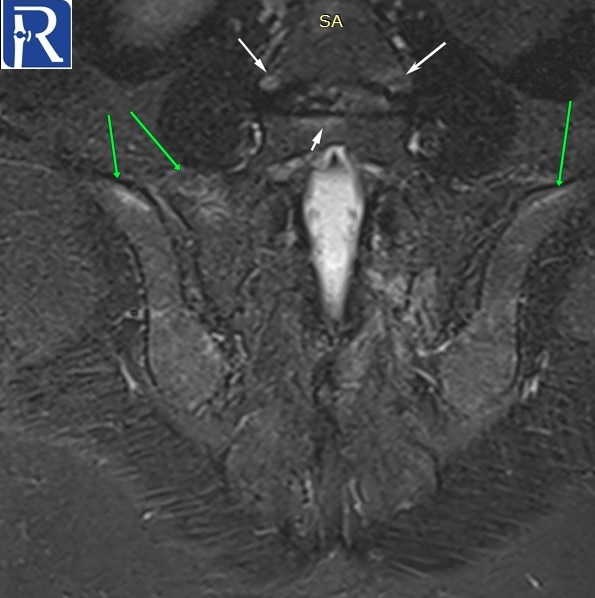

Sacroillitis

Demographic and clinical details: 32-year-old male patient was admitted with low back pain for 5 years.

Image Details: AP pelvis X-ray shows the joint space irregularity and peri-articular sclerosis of bilateral and narrowing of the superior part of the left sacrooiliac joints. There are mltiple erosions in both sides. Findings are consistent with radiographic sacroiliitis according to the New York criteria (Grade II sacroiliitis of right, grade III sacroiliitis of left side). Structural lesions indicated with arrows (fatty metaplasia with white arrows, backfill with the green arrow, erosion with black arrow) are seen on T1 W images. Extensive edema of Active sacroiliitis (Extensive bone marrow edema of osteitis (white arrows) is seen on the STIR image. Findings are consistent with active enthesitis (green arrows) and spondylitis (thin white arrows) are also seen on subsequent coronal STIR images. Active arthritis of left L5-S1 facet joint (blue arrow) and active enthesitis of posterior part of the left iliac bone (green arrow) are seen on the fat-suppressed T2 W image. Radiological findings are consistent with radiographic axial spondyloarthritis (ankylosing spondyloarthritis).